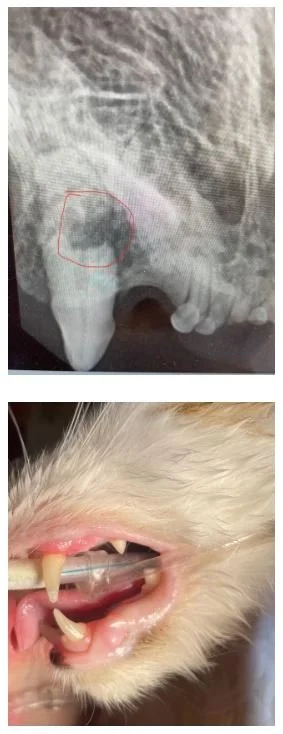

Think of teeth as an iceberg. The majority of the tooth is below the surface which means most of the disease affecting teeth cannot be assessed without looking below the gum line. Without x-rays unfortunately a lot of destructive disease is not caught. Even teeth that look healthy on the surface can be hiding disease below the gum line. For this reason the full mouth should be x-rayed, not just the diseased looking teeth. The picture on the bottom right shows a normal looking canine tooth in a cat mouth. The picture on the top right shows the x-ray of the same tooth with a large lesion just below the gum line with tooth destruction that has made it's way into the highly sensitive pulp cavity. Dental abscesses, bone destruction, and tooth resorption can all cause significant infection and pain without any obvious signs on the tooth surface.

X-ray of a small animal's jaw with a red circle highlighting a specific area, and a close-up photo of a cat's mouth showing dental issues including missing and damaged teeth.